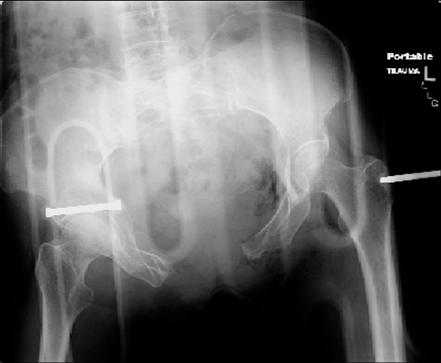

attached are images of a 70 year old female after peds versus car. her own car ran her over.

injuries are limited to the pelvis. left rami open and visible in a 10cm vertical laceration just lateral to left labia majora. wound is grossly clean. no vaginal and no urinary issues. CT scan shows widening of both SI joints anteriorly but I think this is vertically stable pattern.

pt treated that night with I/D and supra-acetabular frame to close the ring. consideration was given for SI screws bilateraly, but given time of night and other factors decision made not to proceed.

so the question is what next operatively if anything? concerns are infection, nonunion anteriorly and possible incompetence of the pelvic floor which may lead to prolapse issues. right rami are comminuted and plating may entail ilioinguinal approach to extend plate laterally to right iliac wing. retrograde screw up right rami is an option but I am not convinced it will add much. adding SI screws very doable, but major concern is restoring anterior ring. so far wound is clean and closed over a drain, and I have no plans to open it back up and wash again.

maintaining pelvic alignment in ex-fix in 70 yo female for any length of time may be challenging.

any thoughts? would anyone plate the pubic symphysis to close the gap and leave the more lateral rami fractures alone? the most recent pelvic case on this website involved pts with suprapubic catheters and antibiotic options including resorbable beads. I wonder how many people would plate and place antibiotic beads. thanks.

attached are several CT cuts. please let me know if you need more. the CT is pre-pelvic ex-fix placement.

Thank you.